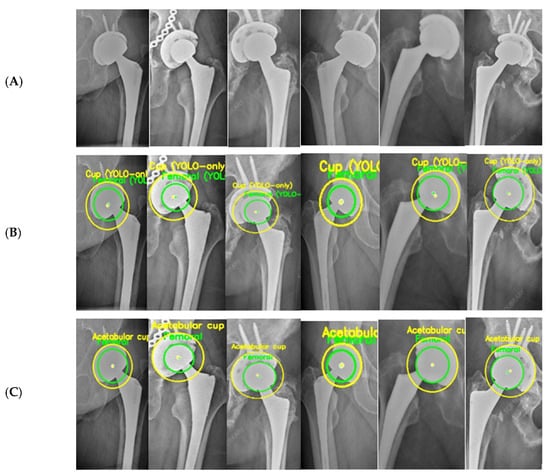

In Figure 12, the PRE radiograph (A) shows the femoral head well-centered within the AC, with a uniform joint space superiorly and medially. The alignment between the two circle centers indicates that no measurable migration has yet occurred. In the POST radiograph obtained several years later (B), the femoral head is positioned closer to the superior aspect of the cup, indicating a clear difference in the superior joint space. This pattern is consistent with progressive superior polyethylene wear. Additionally, a slight medial shift of the femoral head center is visible, demonstrating progressive medial wear over time. Overall, the comparison between (A) and (B) shows a combined superior and medial wear. Similar to Figure 11, the radiographs in Figure 12 were obtained from the external, unseen dataset and were never used for training or validation.

Figure 12.

Example 2 of PRE–POST radiographs with detected femoral head and AC circles. (A) PRE radiograph demonstrating a centered femoral head within the acetabular cup. (B) POST radiograph showing superior displacement of the femoral head consistent with wear progression.

These findings reinforce the value of combining visual and quantitative evidence when interpreting longitudinal THA radiographs. While subtle migration patterns can be difficult to identify through visual inspection alone, particularly when the displacements are only a few pixels, the automated circle-based analysis provides a reproducible framework for detecting even minimal deviations from baseline alignment. The PRE–POST differences captured in Figure 11 and Figure 12 demonstrate how small variations in center position and joint-space geometry accumulate over time to form clinically meaningful wear trajectories. Importantly, the refined circle estimates reduce the influence of image noise, projection variability, and partial rim visibility, ensuring that the observed displacements reflect true anatomical change rather than measurement artifacts. By integrating both geometric overlays and numerical wear metrics, the system enables a clear linkage between qualitative radiographic appearance and quantitative displacement values. This dual-layer interpretation helps distinguish early progressive wear from normal postoperative variation and supports more consistent longitudinal monitoring of implant performance.

Two representative wear cases were quantitatively summarized in Table 3 and Table 4, each including a pair of PRE and POST radiographs along with the automatically computed medial, superior, and resultant wear components. In both examples, the system successfully produced consistent numerical outputs after scale normalization. These examples demonstrate the ability of the proposed framework to extract reliable and fully automated wear measurements. When a magnification factor is available, pixel-based wear values can be converted to millimeters using the following:

Table 4.

Automatic measurements and calculated wear values for Figure 12.